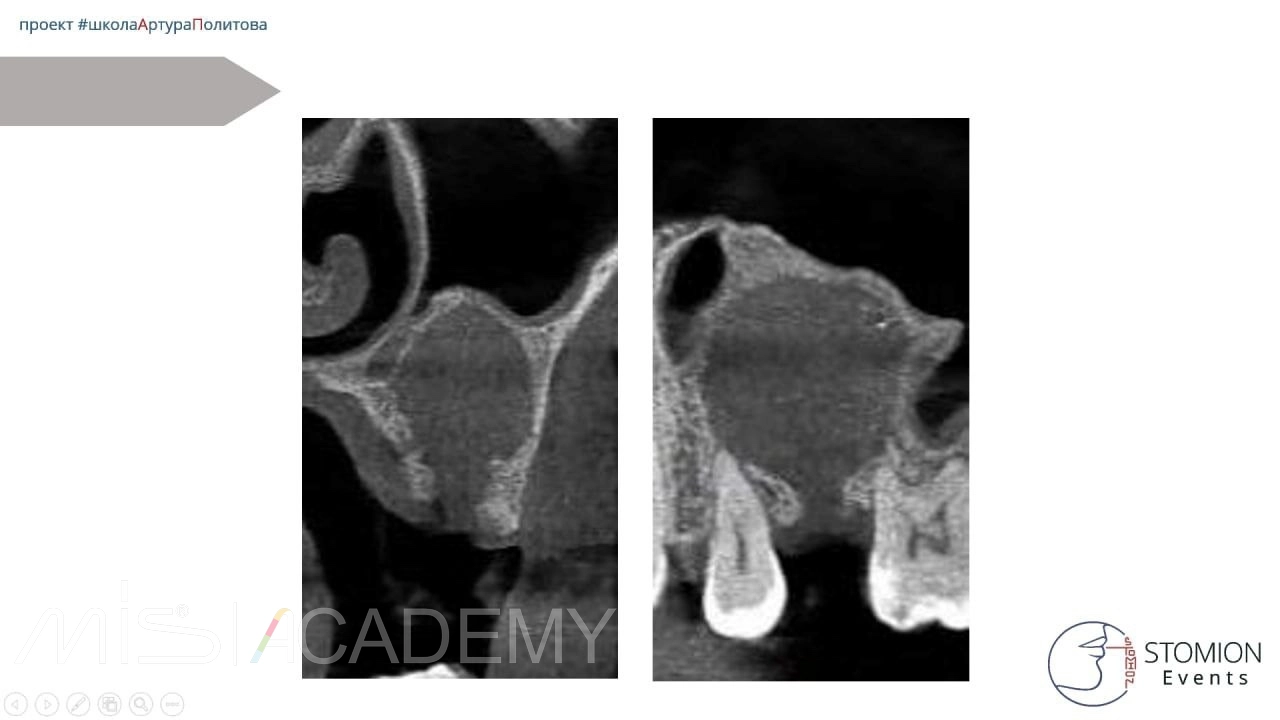

Что мы видим на промежуточном осмотре?

— По данным КЛКТ рентгенологический объём уменьшился, по периметру мы видим формирование нативной кости с кортикализацией.

— По цифровым данным КЛКТ отмечаются зоны до +100-300, что говорит о формировании костных балок.

Далее пациентка пропала с радаров. Через 2,5 года на КЛКТ мы видим полное восстановление костной ткани, восстановление синуса. Это очередная победа декомпрессии над привычными методами.